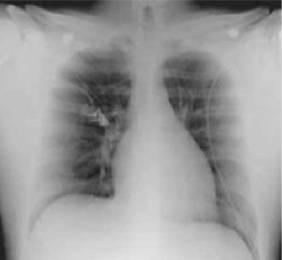

Radiografía de Tórax:

- Sin alteraciones.